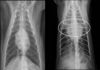

What is shown in these images?

generalized cardiomegaly